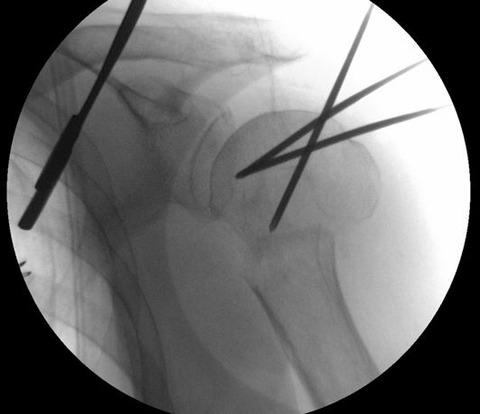

髄内釘のエントリーポイントを至適にするためには、転位した上腕骨頭を整復する必要があります。私は2.4 K-wireを肩峰外側から上腕骨頭に2本刺入して、これをjoy-stickにして整復します。

まず、1本目の2.4 K-wireを肩峰下に沿ってできるだけ上腕骨頭内側に進めます。この際、どうしても肩峰の外側が邪魔になるのですが、ある程度仕方ありません。

1本目の2.4 K-wireをできるだけ上腕骨頭内側に刺入して、これをjoy-stickにして整復します。しかし1本では整復力が弱いので2本目を刺入して、更に強力に整復を行います。

2本のK-wireをjoy-stickにして思いっきり整復します。上腕骨頭を内転位に保ちながら、上腕骨頭の頂点からガイドワイヤーを刺入します。

K-wireで上腕骨頭を内転位に整復位を保っておかないと腱板に牽引されて外転転位してしまい、髄内釘のエントリーポイントがかなり大結節寄りになってしまいます。

髄内釘のエントリーポイントが大結節寄りになりすぎると、ネイル挿入時に骨折を併発したり、髄内釘の固定力が落ちるので注意が必要です。この手術で一番重要なポイントだと思います。